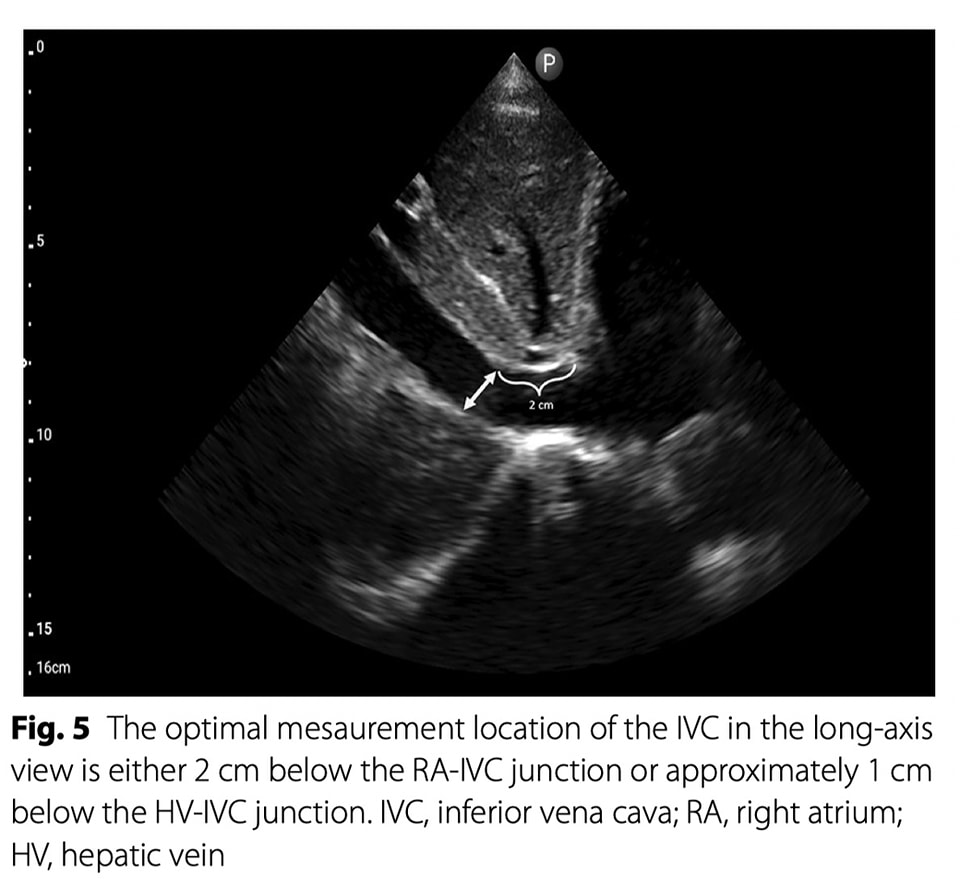

🔴A practical guide in #POCUS assessment of venous congestion ⤵️ #2024Review #OpenAccess 🔹The optimal mesaurement location of the IVC in the long-axis view is either 2 cm below the RA-IVC junction or approximately 1 cm below the HV-IVC junction. 🔹 https://t.co/pNcHXOjQPa